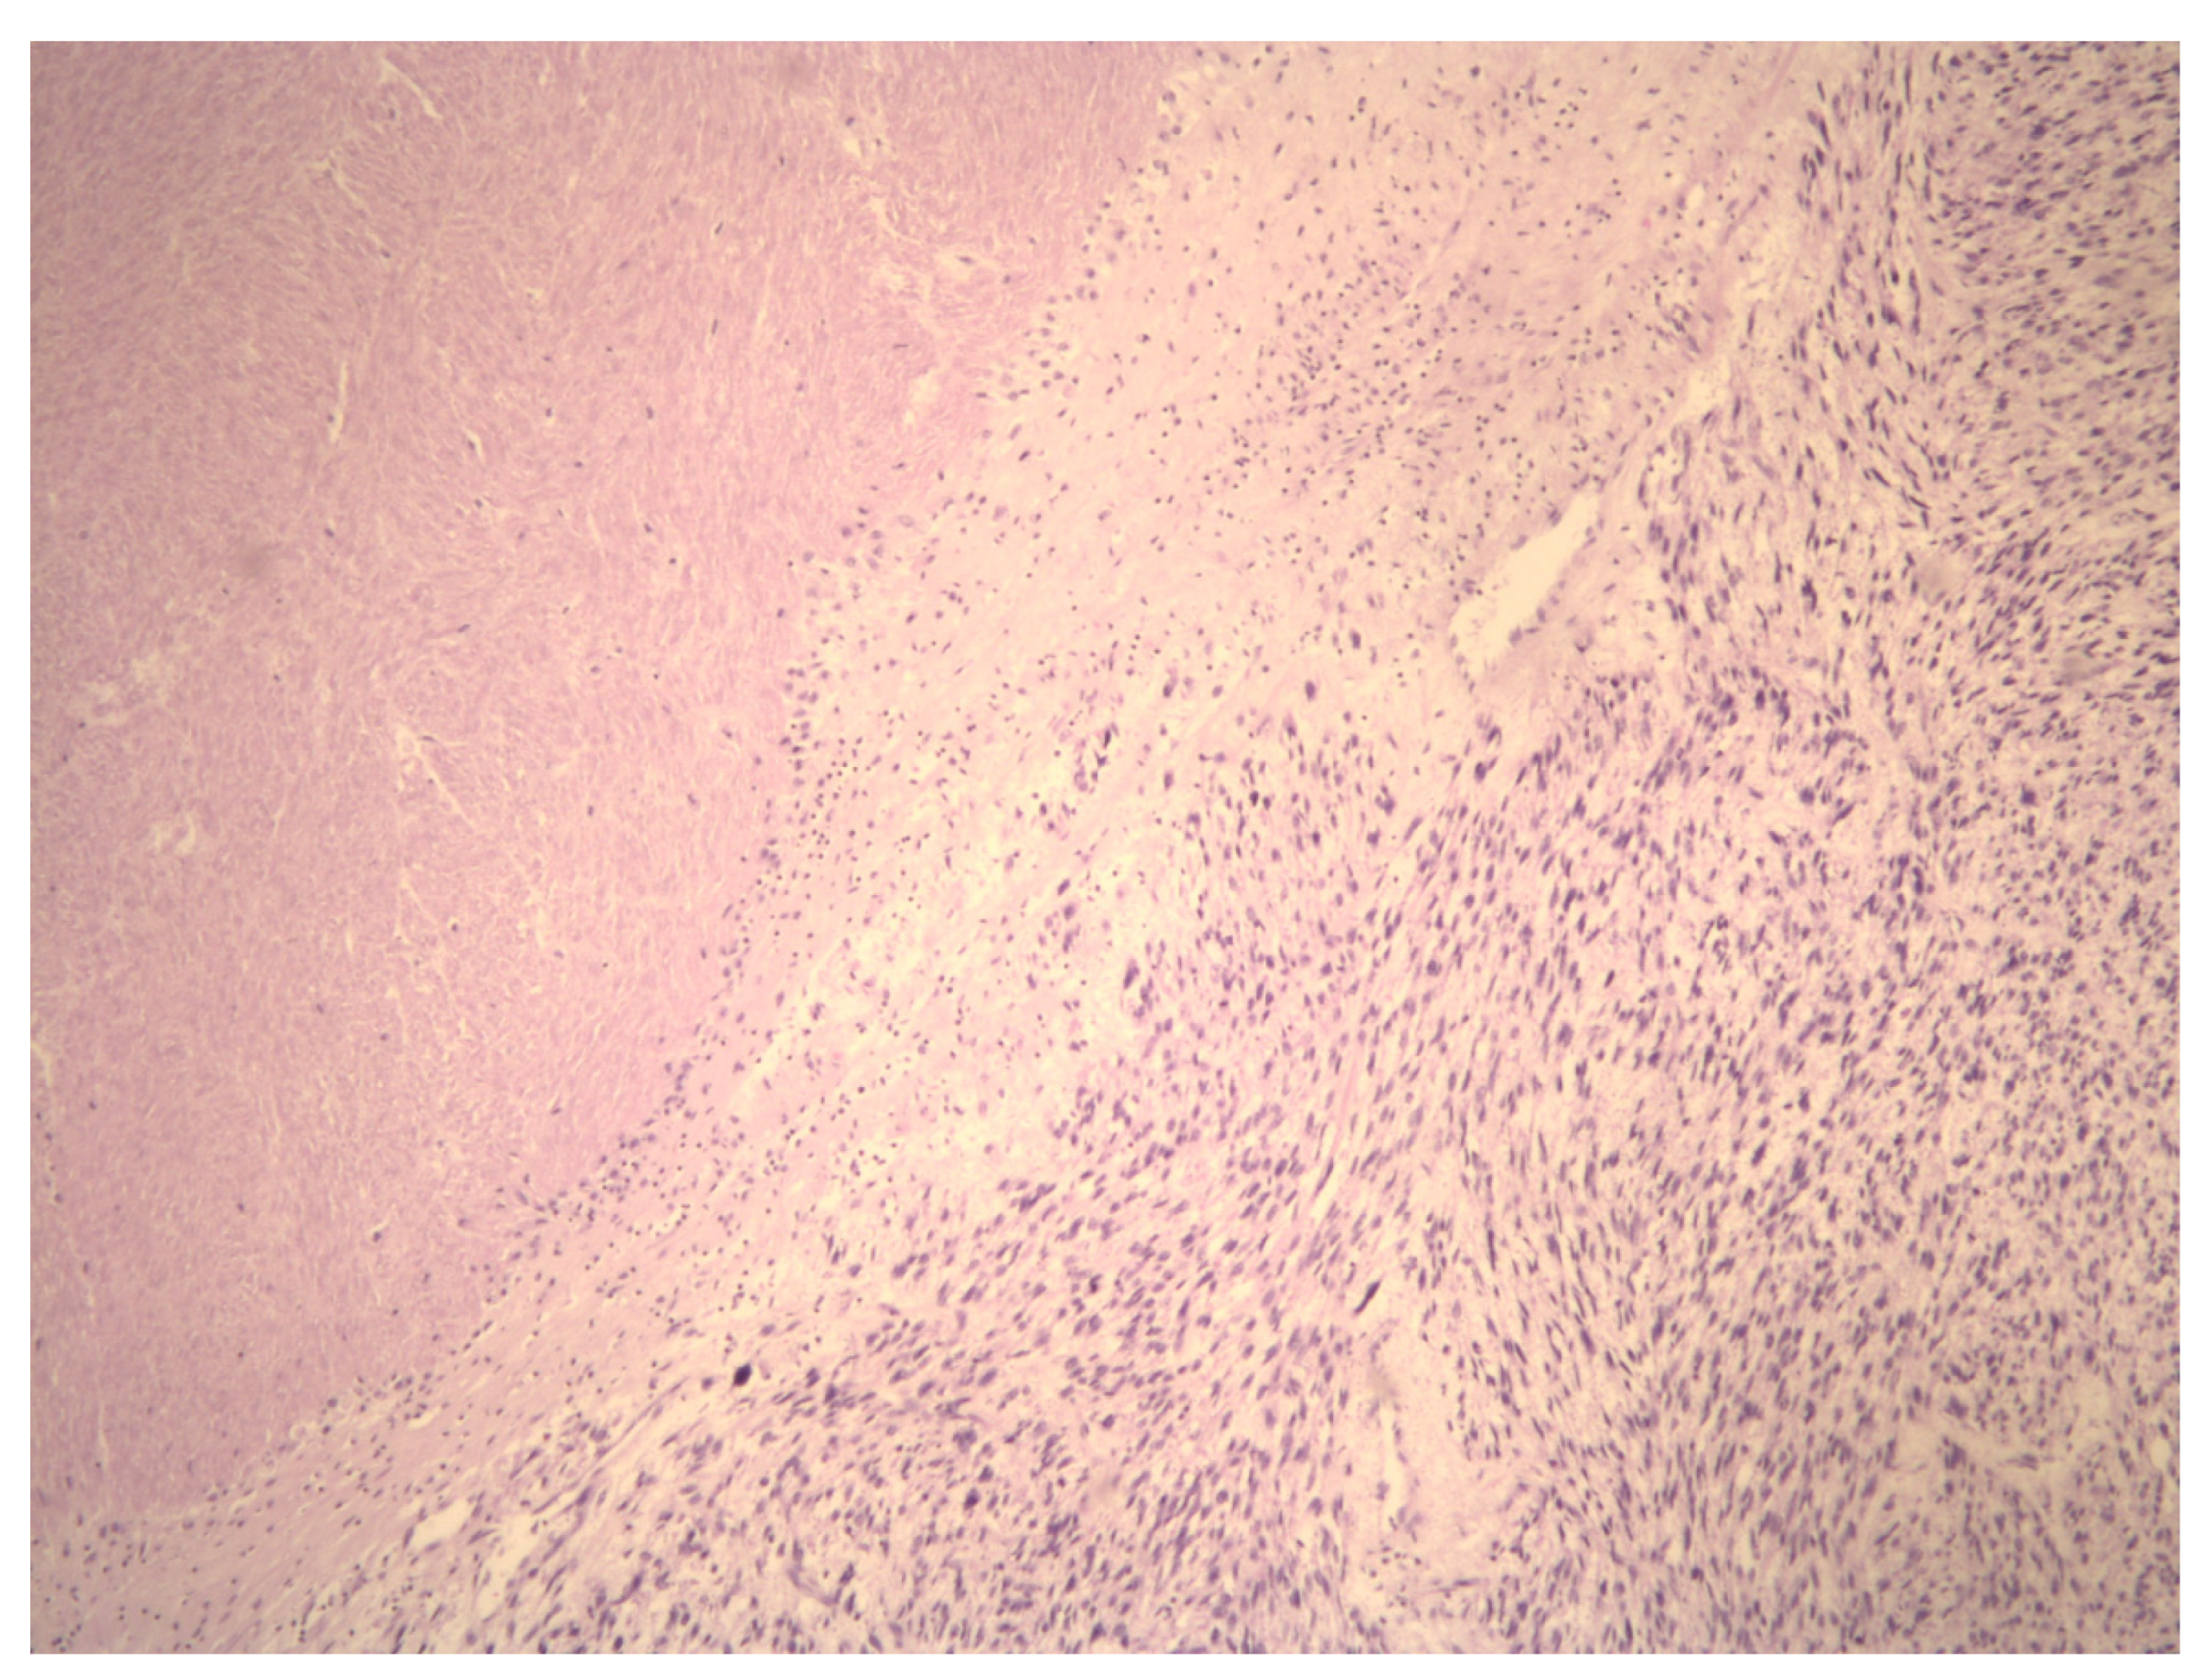

Molecular Insights in Uterine Leiomyosarcoma: A Systematic Review

3.2. Molecular Basis of Differentiation Uterine Leiomyosarcoma vs. Uterine Leiomyoma